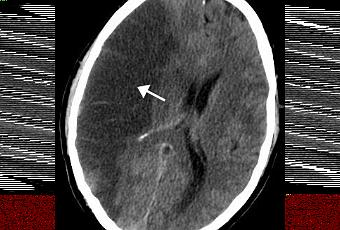

AVC ischémique

Source iconographique: https://simple.wikipedia.org/wiki/Stroke